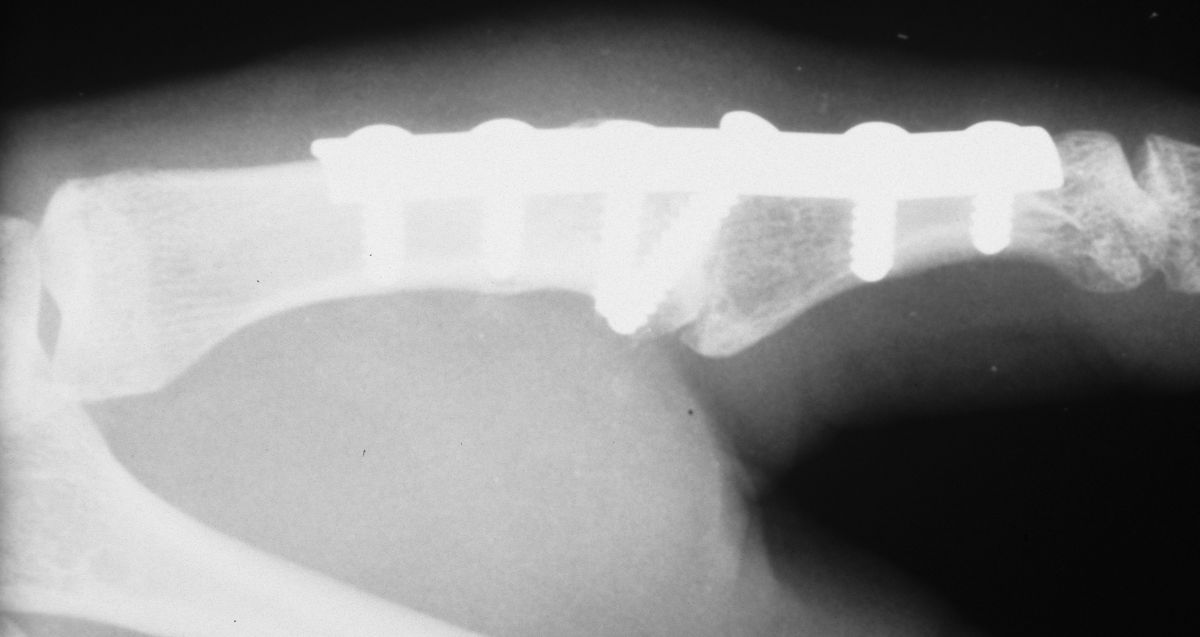

| Final Result |